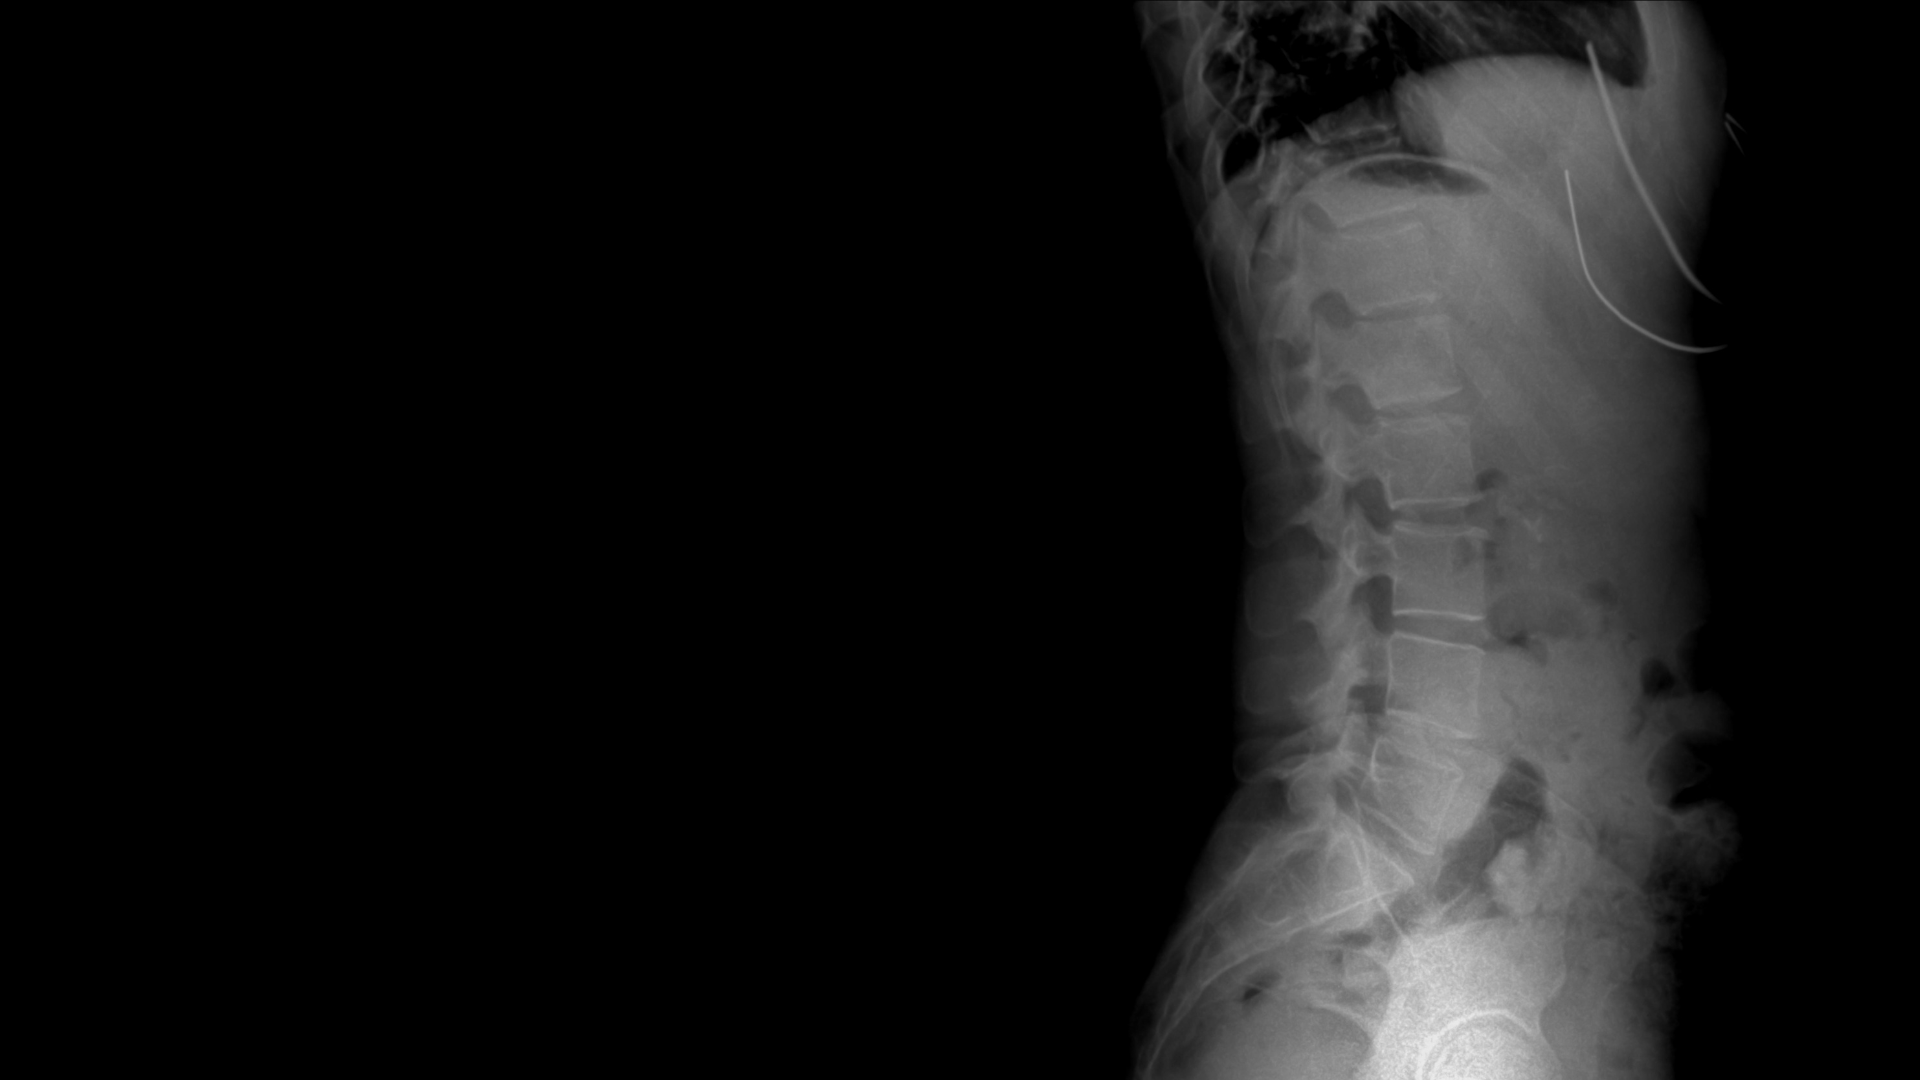

Courtney had a 50 degree curve T6-T11 before having spinal fusion in 2002 via thoracotomy, bringing the curve to 7 degrees. A second curve developed in 2018 from T5-L2 of 40 degrees which can be seen in the photo on the left. With a steel rod in the thoracic spine, there is a limitation to what we are able to do. This is why it is SO important to address the underlying course and structure and avoid surgical bandaids when it comes to scoliosis.